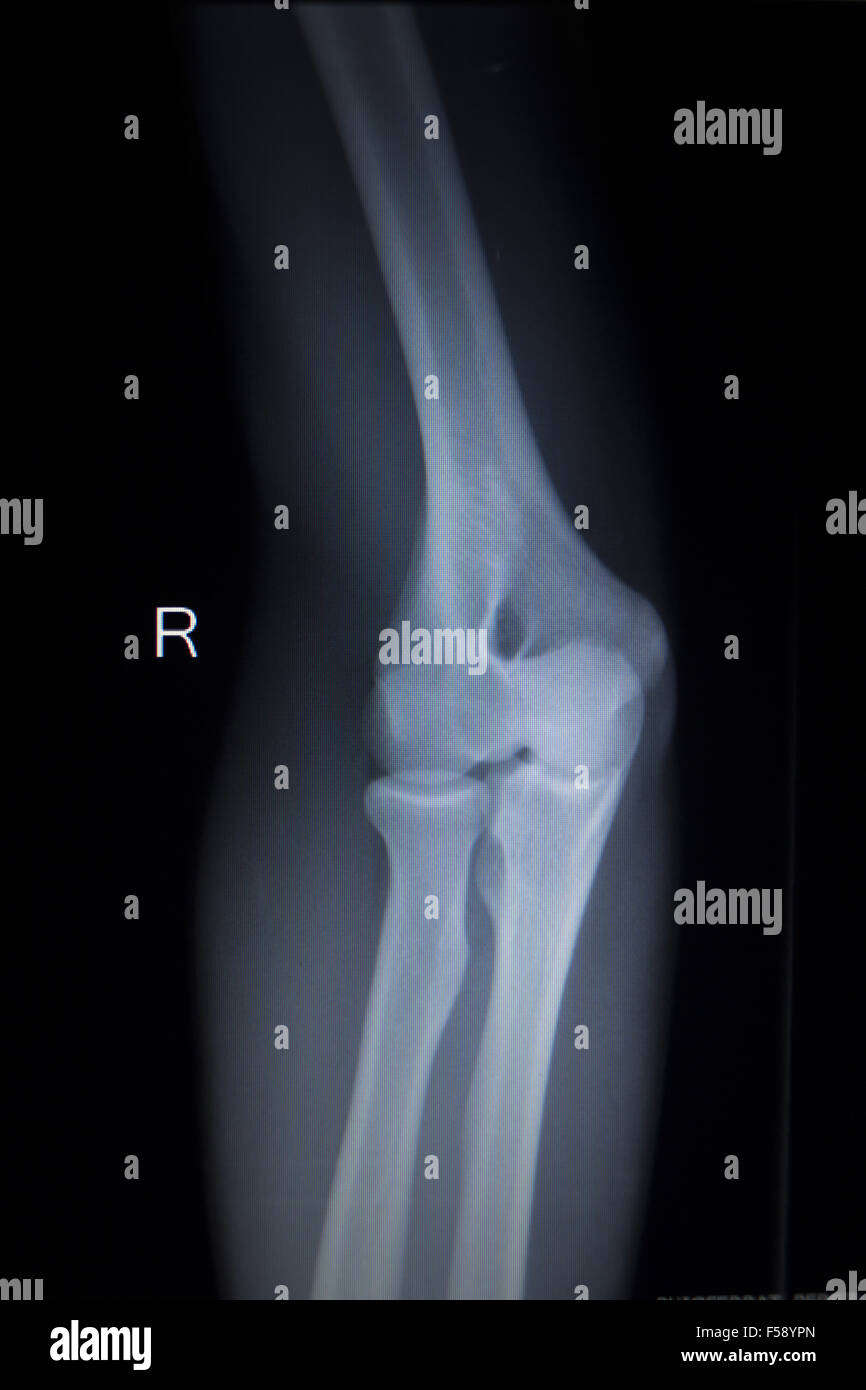

From www.alamy.com

Xray orthopedic medical CAT scan of painful tennis elbow injury in Cat Elbow X-Ray 11 elbow luxations, therefore, usually require. Based on cadaveric cat studies, both medial and lateral collateral ligaments need to be damaged for elbow luxation to occur. The imaging anatomy web site is a basic atlas of normal imaging anatomy of domestic animals. It is designed as an aid for. For the orthogonal image, the elbow is imaged in a craniocaudal. Cat Elbow X-Ray.